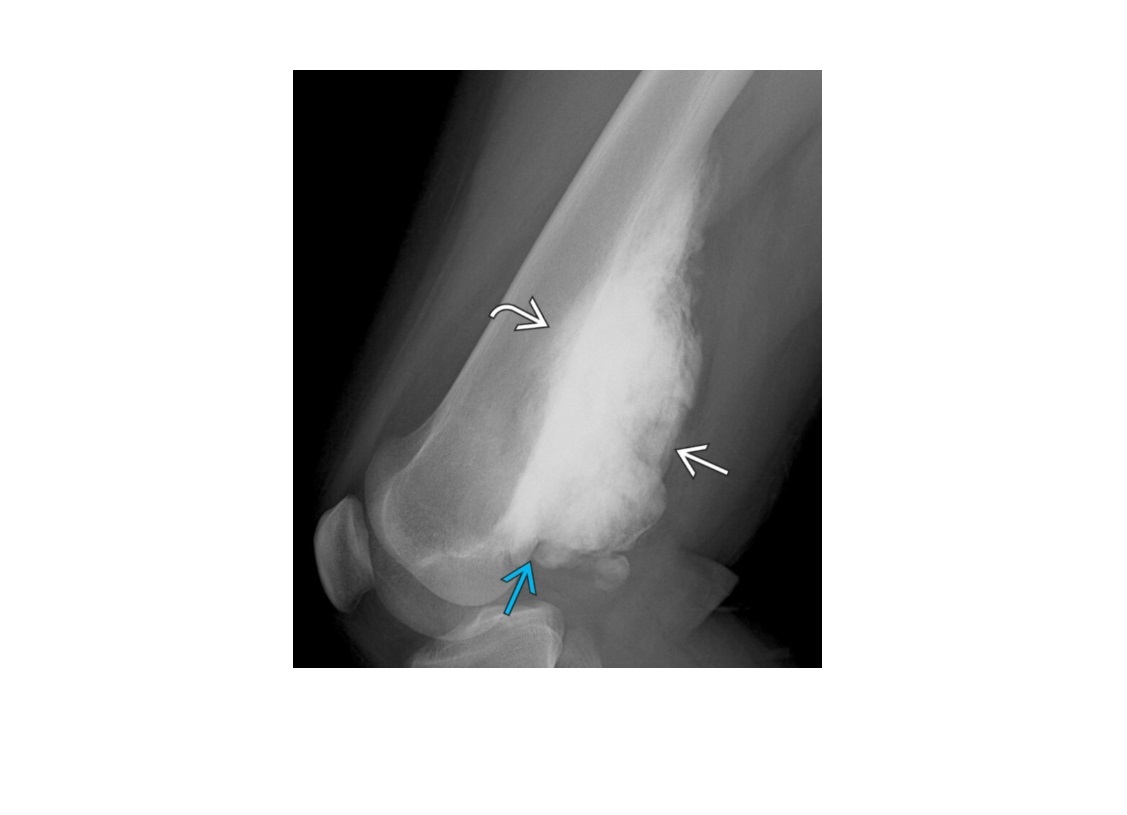

Segond fracture

Lateral tibial plateau

Associated with ACL tear (75%) and internal rotation

Arcuate sign

Avulsion of the proximal fibula

Associated with PCL tear